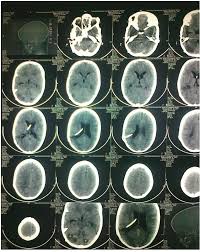

Vp Shunt Ct Scan

Radiological Findings Before And After Vp Shunt Placement Notes A Download Scientific Diagram